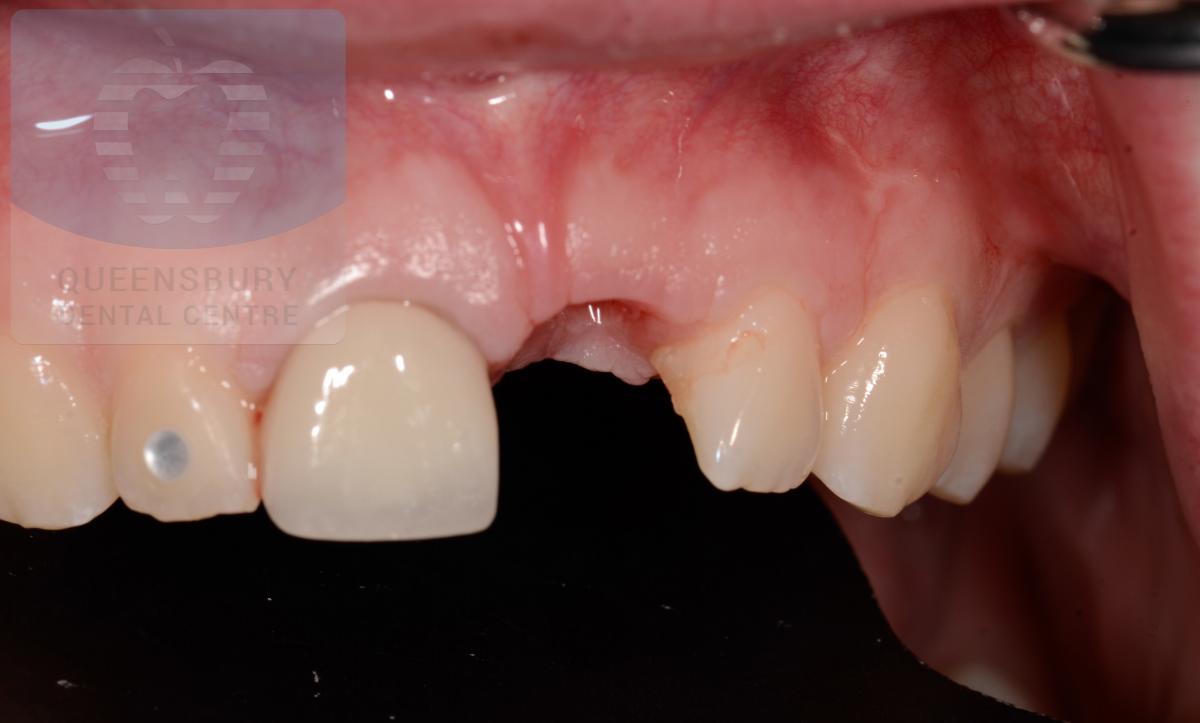

Missing teeth and loose dentures make many people avoid social settings because they are too self-conscious about their appearance. Current dental procedures, however, replace everything from a single missing tooth to a completely missing arch. Ask your dentist or dental specialist about the different dental options that are available to you. Don’t let another day go by without taking this important first step to restoring your confidence and your smile!